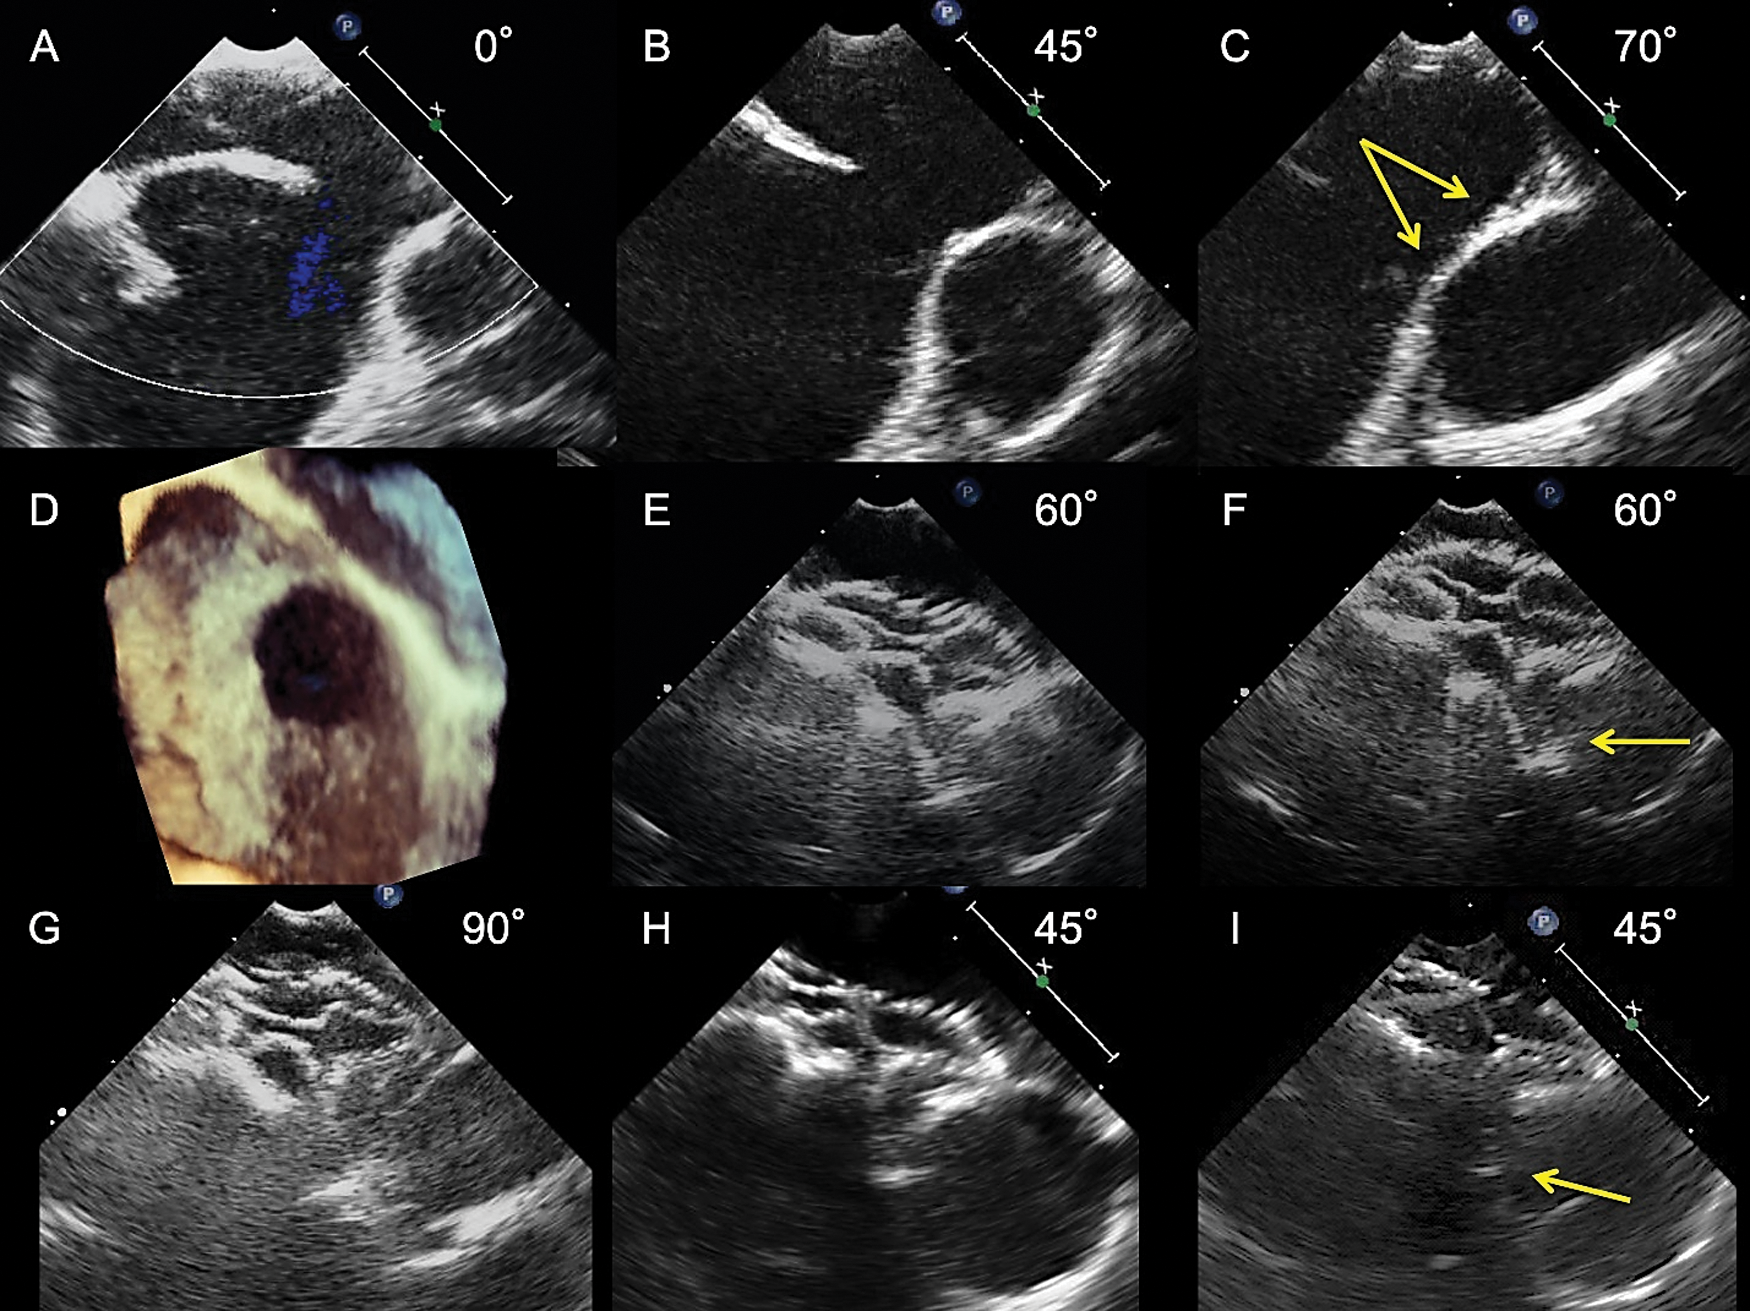

Figure 1: Transesophageal echocardiograms showing the process of selecting an FFII to shape the two discs flared and straddling behind the aorta. An 8-year-old boy weighing 21 kg had a 13.9 mm × 11.5 mm ASD with a 0.5 mm-length aortic rim in a wide area only (A, B, D) and a malaligned no superior rim (C, arrows, and D). A 21 mm FFII was placed into the ASD for a BSD of 16.6 mm. Immediately after placement (E, the farthest phase of the device from the Valsalva; F, the nearest phase of the device), two discs were flared and straddling over the Valsalva (E, F) and the superior side (G). The device looks flexible and bulky, and not the edge but the inner plane of the right atrial disc is slightly pressing the Valsalva wall intermittently (F, arrow). At 6 months after placement (H: Farthest phase, I: Nearest phase), the device shape becomes compact, but the two discs are kept flared and straddling behind the aorta; hence, the right atrial disc inner plane is slightly pressing the Valsalva wall intermittently (I, arrow)

Figure 5: Transesophageal echocardiograms showing the inner plane of the disc pressing the Valsalva wall. A 30 mm FFII device was placed into the ASD for a BSD of 23.3 mm in an 8-year-old boy who had a 20 mm diameter ASD with an absent aortic rim in multiple views and bald aorta (A). Immediately after placement (C, the farthest phase of the device from the Valsalva; D, the nearest phase of the device), the whole device shape looks bulky, with two discs flared and straddling over the Valsalva and the inner plane of the right atrial disc slightly pressing the Valsalva wall intermittently, even though the maximum depth of the deformation is only 1.0 mm (D, arrow). At 6 months after placement (E, farthest phase; F, nearest phase), the whole device shape became compact, but the two discs became more flared over the Valsalva. Hence, the discs do not seem to be pressing the Valsalva wall

Figure 6: Transesophageal echocardiograms showing the disc edge perpendicularly pressing the Valsalva wall. A 45-year-old female had a 17.4 mm diameter ASD with absent aortic rim in multiple views, bald aorta, and malaligned aortic rim (A, B, arrow). A 27 mm FFII device was placed into the ASD for a 22 mm BSD. Immediately after placement (C, the farthest phase of the device from the Valsalva, D, the nearest phase of the device), the two discs flared but were not straddling enough over the Valsalva. Hence, the right atrial disc edge is perpendicularly pressing the Valsalva wall intermittently, even though the maximum depth of the deformation is only 1.0 mm (D, arrow). At 6 months after placement (E, farthest phase; F, nearest phase), the whole device becomes compact, the two discs remain flared without straddling enough over the Valsalva and the right atrial disc edge is still intermittently pressing the Valsalva wall, even though the maximum depth of the deformation is only 1.3 mm (F, arrow)